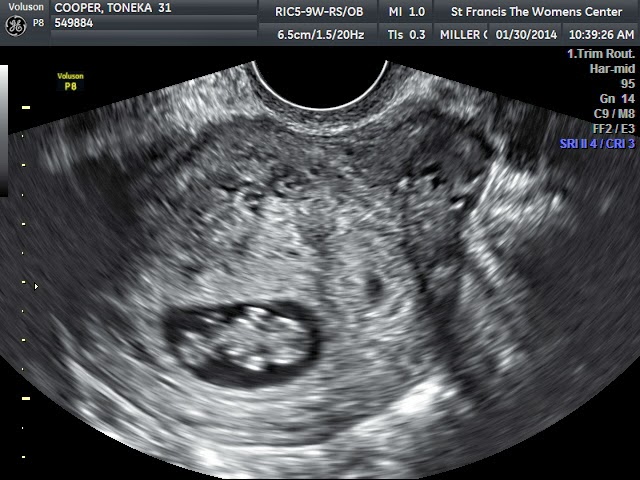

I went into the midwifes office and got ready for the Ultrasound.  She kept staring at the screen like something was wrong at first and my heart was pounding out of my chest!  Then she let me know that she could see the baby...but it was not a clear photo and she needed me to get dressed and move next door to the doctors office because he had a better ultrasound machine.  When we got set up in there my midwife says, "I thought I was seeing two heartbeats on the other machine but the image wasn't very good!"  The doctor looks around for what seemed like FOREVER, then says, "I'm only seeing one, unless there is one hiding somewhere."  Then they looked a little longer and it was decided they were PRETTY sure there was only one, but I'm to come back in a few weeks to have another ultrasound when the baby is a little bigger.  But the best part of all-  There was a heartbeat!!!!  My prayers were all answered in that one moment when I saw that little beat of a heart!